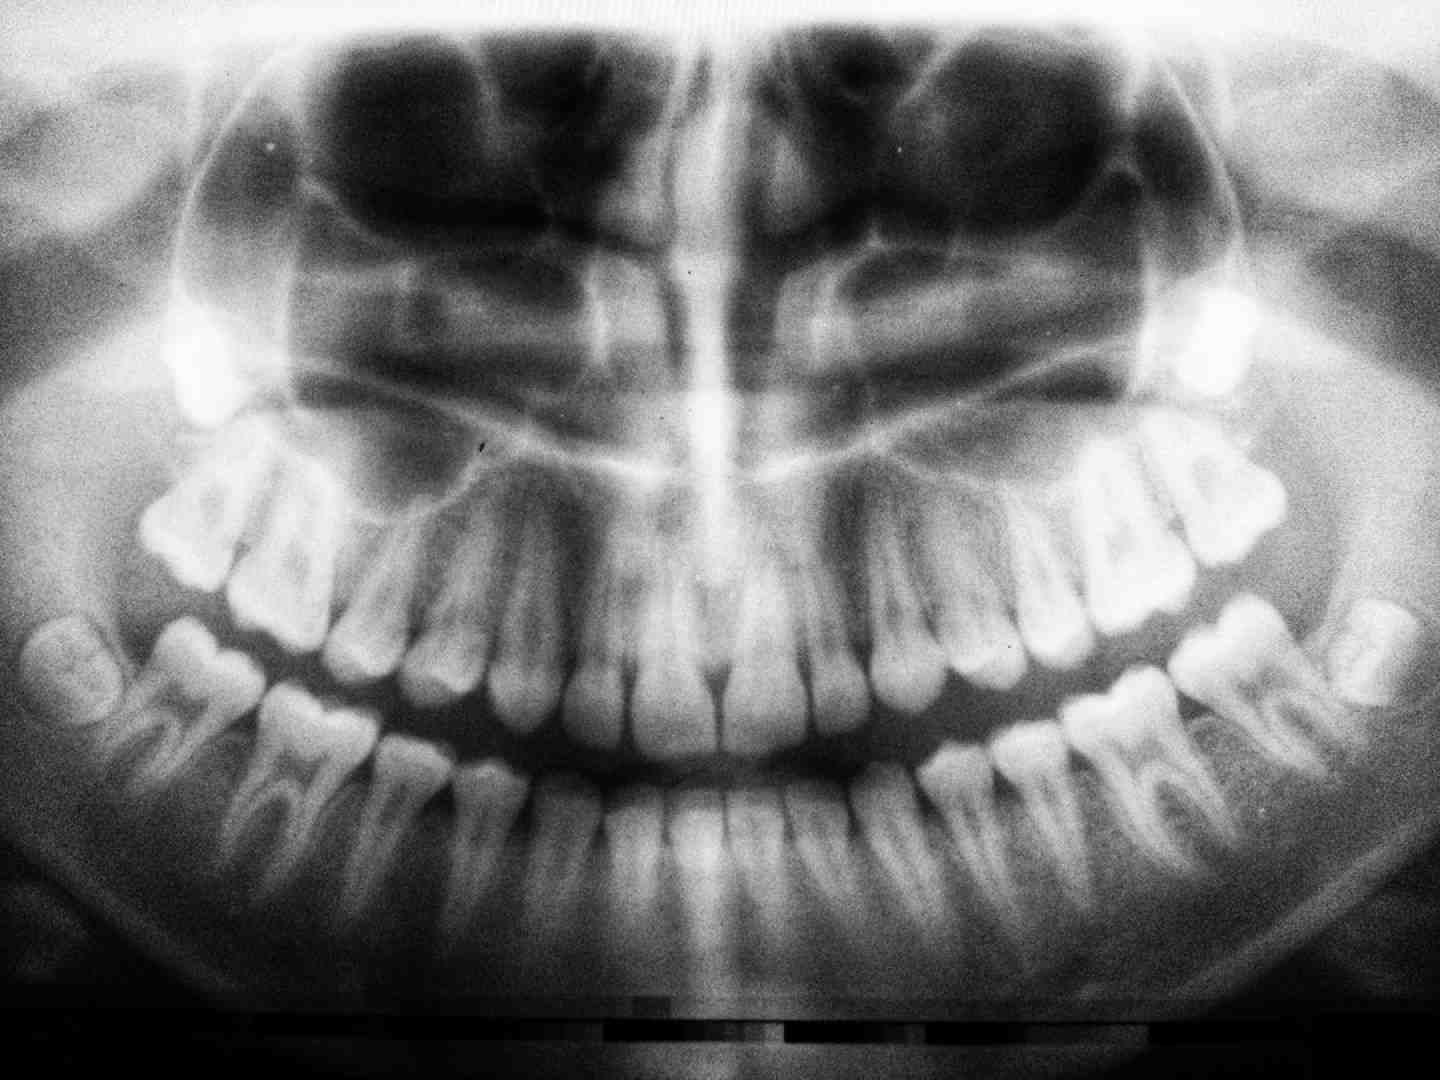

What are dental implants

When oral hygiene fails, both teeth (or dental implants) and surrounding tissues (gum, periodontium, and alveolar bone) are exposed to major pathogens, which can lead to decay, gingivitis, periodontitis, or peri. -implantitis.